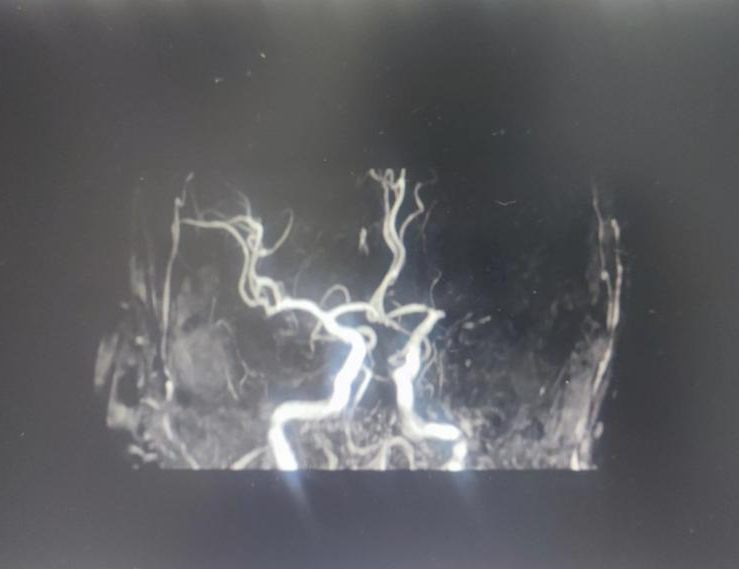

頭顱MRA:左大腦中動(dòng)脈閉塞

4號(hào)早上8點(diǎn)半,呼叫鈴又響起。家人發(fā)現(xiàn)徐大爺再次出現(xiàn)嗜睡等癥狀,情況危急,郭春暉主任判斷徐大爺?shù)难艹霈F(xiàn)了再發(fā)閉塞。頭顱MRI+MRA顯示徐大爺側(cè)腦室旁腦白質(zhì)變性,腦萎縮;顱內(nèi)動(dòng)脈粥樣硬化,局部管腔狹細(xì);左大腦中動(dòng)脈閉塞,兩側(cè)胚胎型大腦后動(dòng)脈。